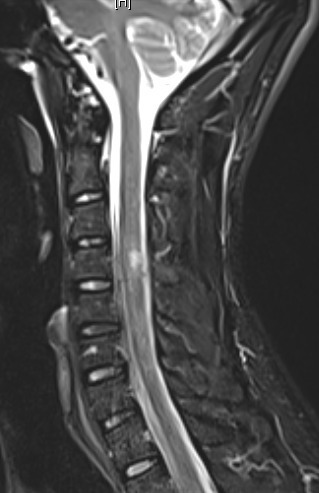

Dissémination spatiale : plusieurs territoires atteints cliniquement, au moins deux territoires atteints en IRM parmi : le territoire périventriculaire, le trajet des nerfs optiques, la région sous/juxta- et intracorticale, la fosse postérieure, la moelle épinière. Particularité des nouveaux critères : prendre en compte les lésions de la fosse postérieure et de la moelle symptomatiques.

Dissémination temporelle : plusieurs poussées cliniques dans le temps, apparition de nouvelles lésions entre les IRM, ou certaines lésions prennent le contraste et pas d’autres sur une même IRM, ou apparition d’une synthèse intrathécale dans le LCS.